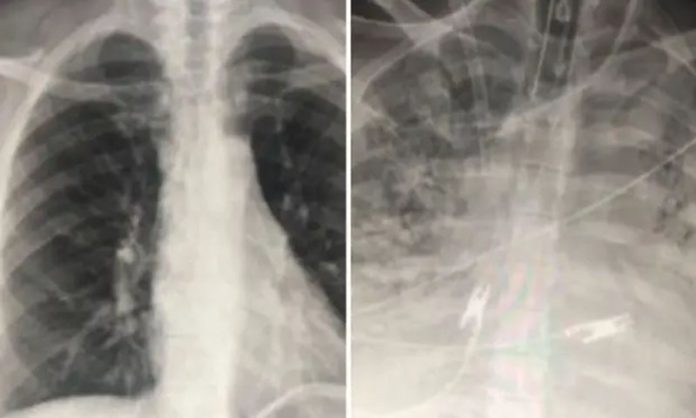

Britanski Mirror objavio je fotografije rendgena dva pacijenta, oba zaražena koronom, ali jedan je vakcinisan, a drugi nije.

- Ozbiljno obolijevaju jedino nevakcinisani. Njima često trebaju kisik ili moraju na respirator. Vakcinisani pacijenti zaraženi koronom imaju bolji protok zraka u plućima i veći dio pluća obojen im je u crno na ovim snimkama, što znači da je šteta na plućima mala ili nikakva – objasnio je doktor Sam Durrani za Mirror.

S druge strane, kod nevakcinisanog pacijenta vidi se da su pluća jako zahvaćena, oštećena i da je protok zraka ograničen.

- Kad nam dolaze pacijenti koji su vakcinisani i zaraženi koronom, čak i nakon što im se stanje pogorša i dobiju upalu pluća, stavimo ih na CT i snimke nisu ni blizu loše kao one nevakcinisanih – rekao je doktor i dodao kako vakcina uspješno štite pacijente od težeg oblika bolesti i smrti kod većine ljudi koji dobiju koronu, prenosi Mirror.